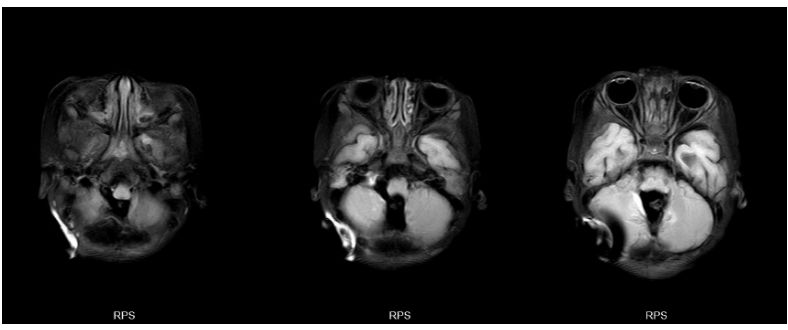

头颅增强磁共振提示:第四脑室区肿瘤,伴幕上脑积水、间质性脑水肿,肿块包绕基底动脉,室管膜瘤首先考虑。

图2. 头颅MR增强:见后颅窝肿块轻度强化,四脑室出口生长进入脑干侧前方,包绕椎动脉、小脑后下动脉等分支,向下延伸进入椎管内。